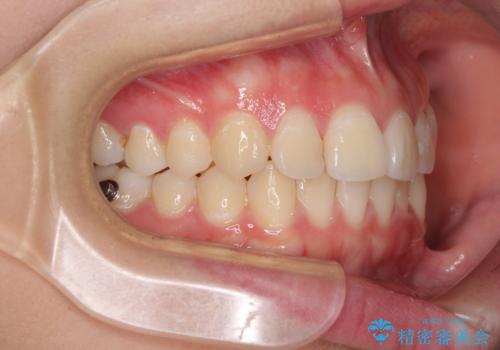

前歯のデコボコを改善 インビザライン矯正

- 口元のデコボコを気にして来院された患者様です。

前歯の捻れにより口元が閉じにくくなっていたため、歯列全体の側方への拡大と、歯と歯の間を少し削ってスペースを獲得することとしました。

ゴムかけをしっかりと行ってもらい、スッキリとした口元に仕上げることができました。